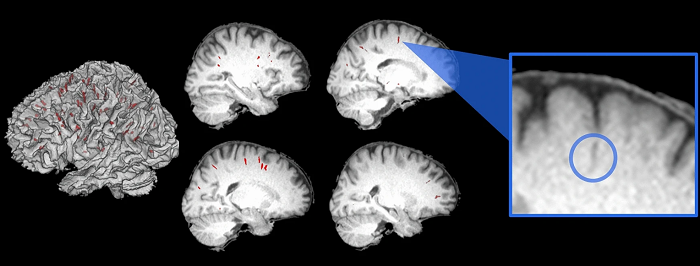

Los investigadores utilizaron imágenes de resonancia magnética para medir el espacio perivascular, o el espacio alrededor de los vasos sanguíneos, en los cerebros de los astronautas antes de su lanzamiento y nuevamente inmediatamente después de su regreso. También volvieron a tomar mediciones de resonancia magnética al mes, tres y seis meses después de haber regresado. Las imágenes de los astronautas se compararon con las tomadas del mismo espacio perivascular en los cerebros de 16 sujetos de control en la Tierra.

Comparando imágenes de antes y después, encontraron un aumento en los espacios perivasculares dentro de los cerebros de los astronautas primerizos, pero ninguna diferencia entre los astronautas que sirvieron previamente a bordo de la estación espacial que orbita la Tierra.

Los espacios perivasculares medidos en el cerebro equivalen al "hardware" subyacente del sistema glinfático. La ampliación de estos espacios se produce en el envejecimiento y también se ha asociado con el desarrollo de la demencia.

Los investigadores utilizaron una técnica desarrollada en el laboratorio de la coautora Lisa C. Silbert, M.D., M.C.R., profesora de neurología en la Escuela de Medicina de OHSU, para medir los cambios en estos espacios perivasculares a través de resonancias magnéticas.